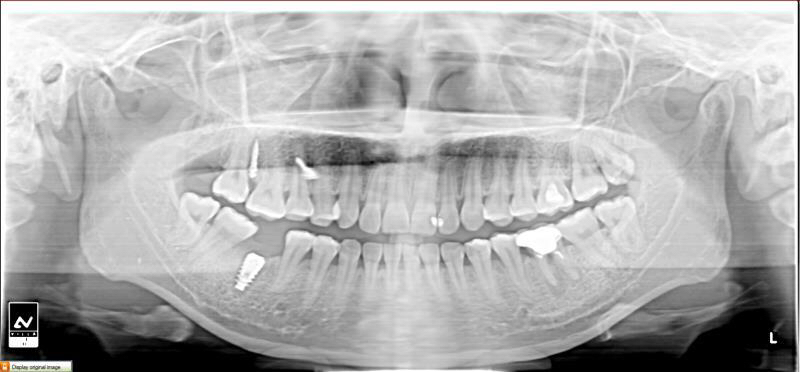

今天给大家介绍一个单颗后牙种植+局部正畸联合治疗病例。

患者年轻女性,后下6残根,因未及时修复,5、7号牙向6号牙倾斜,导致了修复空间不足。按照常规治疗方案,会损伤两侧的健康牙齿,得不偿失,所以我们为她采用了正畸+种植联合治疗方案。